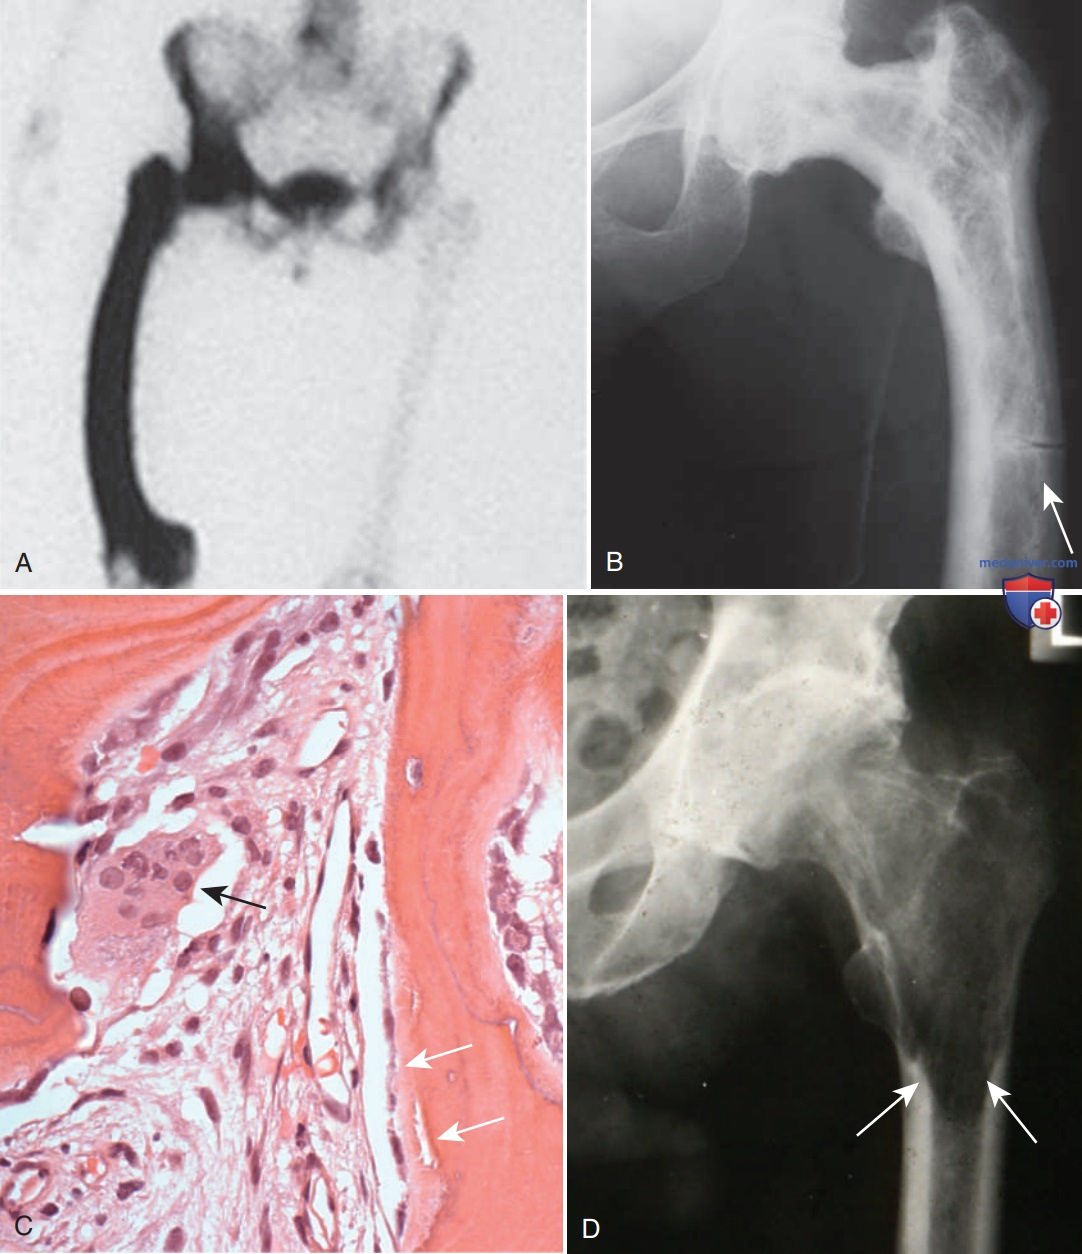

Болезнь педжета кости